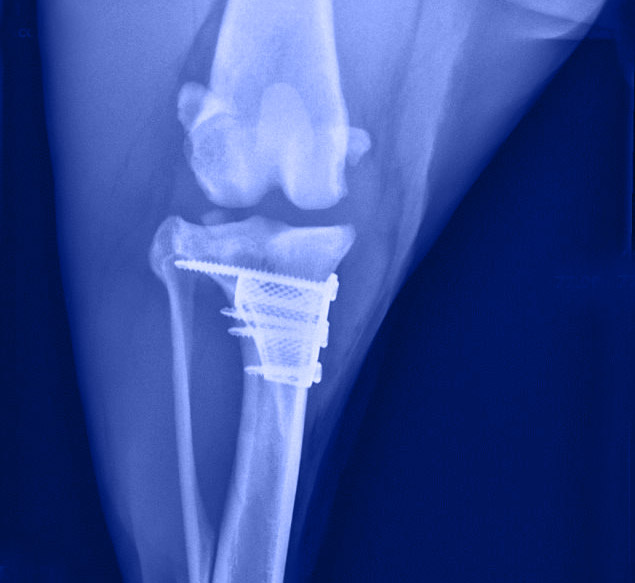

L’orthopédie est une discipline rigoureuse nécessitant beaucoup de matériel. Nos investissements en orthopédie sont constants.

Comme dans toute discipline, les techniques et les moyens mis en œuvre évoluent également. C’est pourquoi notre centre hospitalier vétérinaire essaie de vous offrir les dernières évolutions disponibles.

- Chirurgie des ligaments dont ligament croisé antérieur TPLO, TTA, …